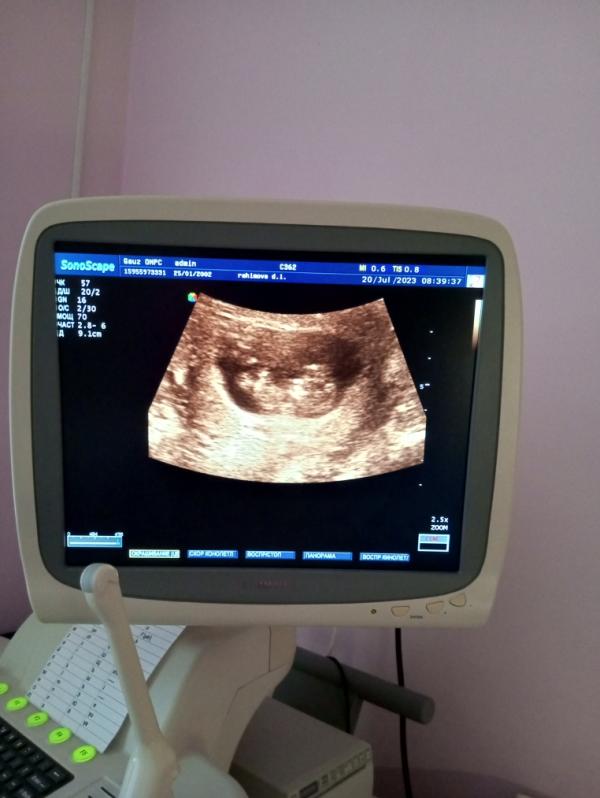

А вот ляля, говорят все нормально 🙏☘️

169 ударов в минуту чсс